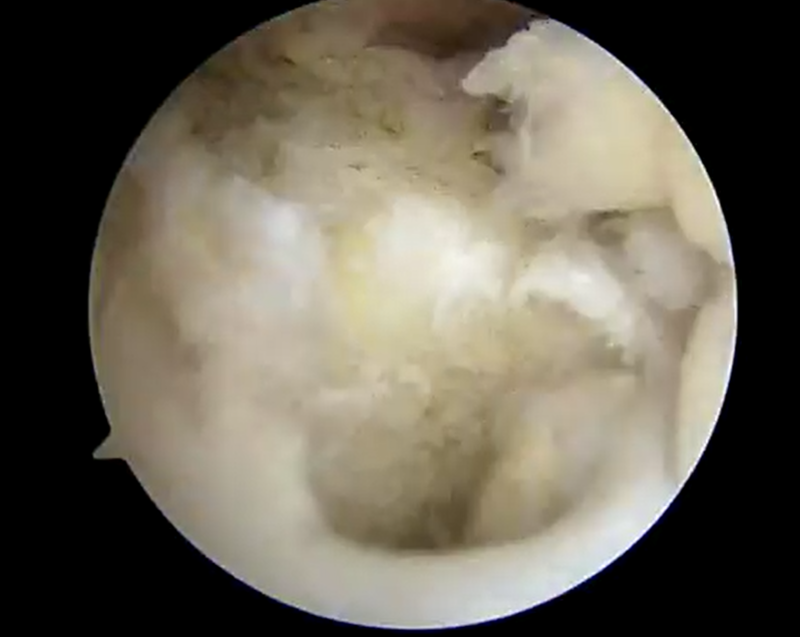

手術所見

![]() ![]() | ![]() ![]() | ![]() ![]() |

| 前十字靭帯損傷部 | 大腿骨側骨孔作成 | 脛骨骨孔作成 |

| 外側半月板問題なし | 内側半月板問題なし | 再建靭帯 |